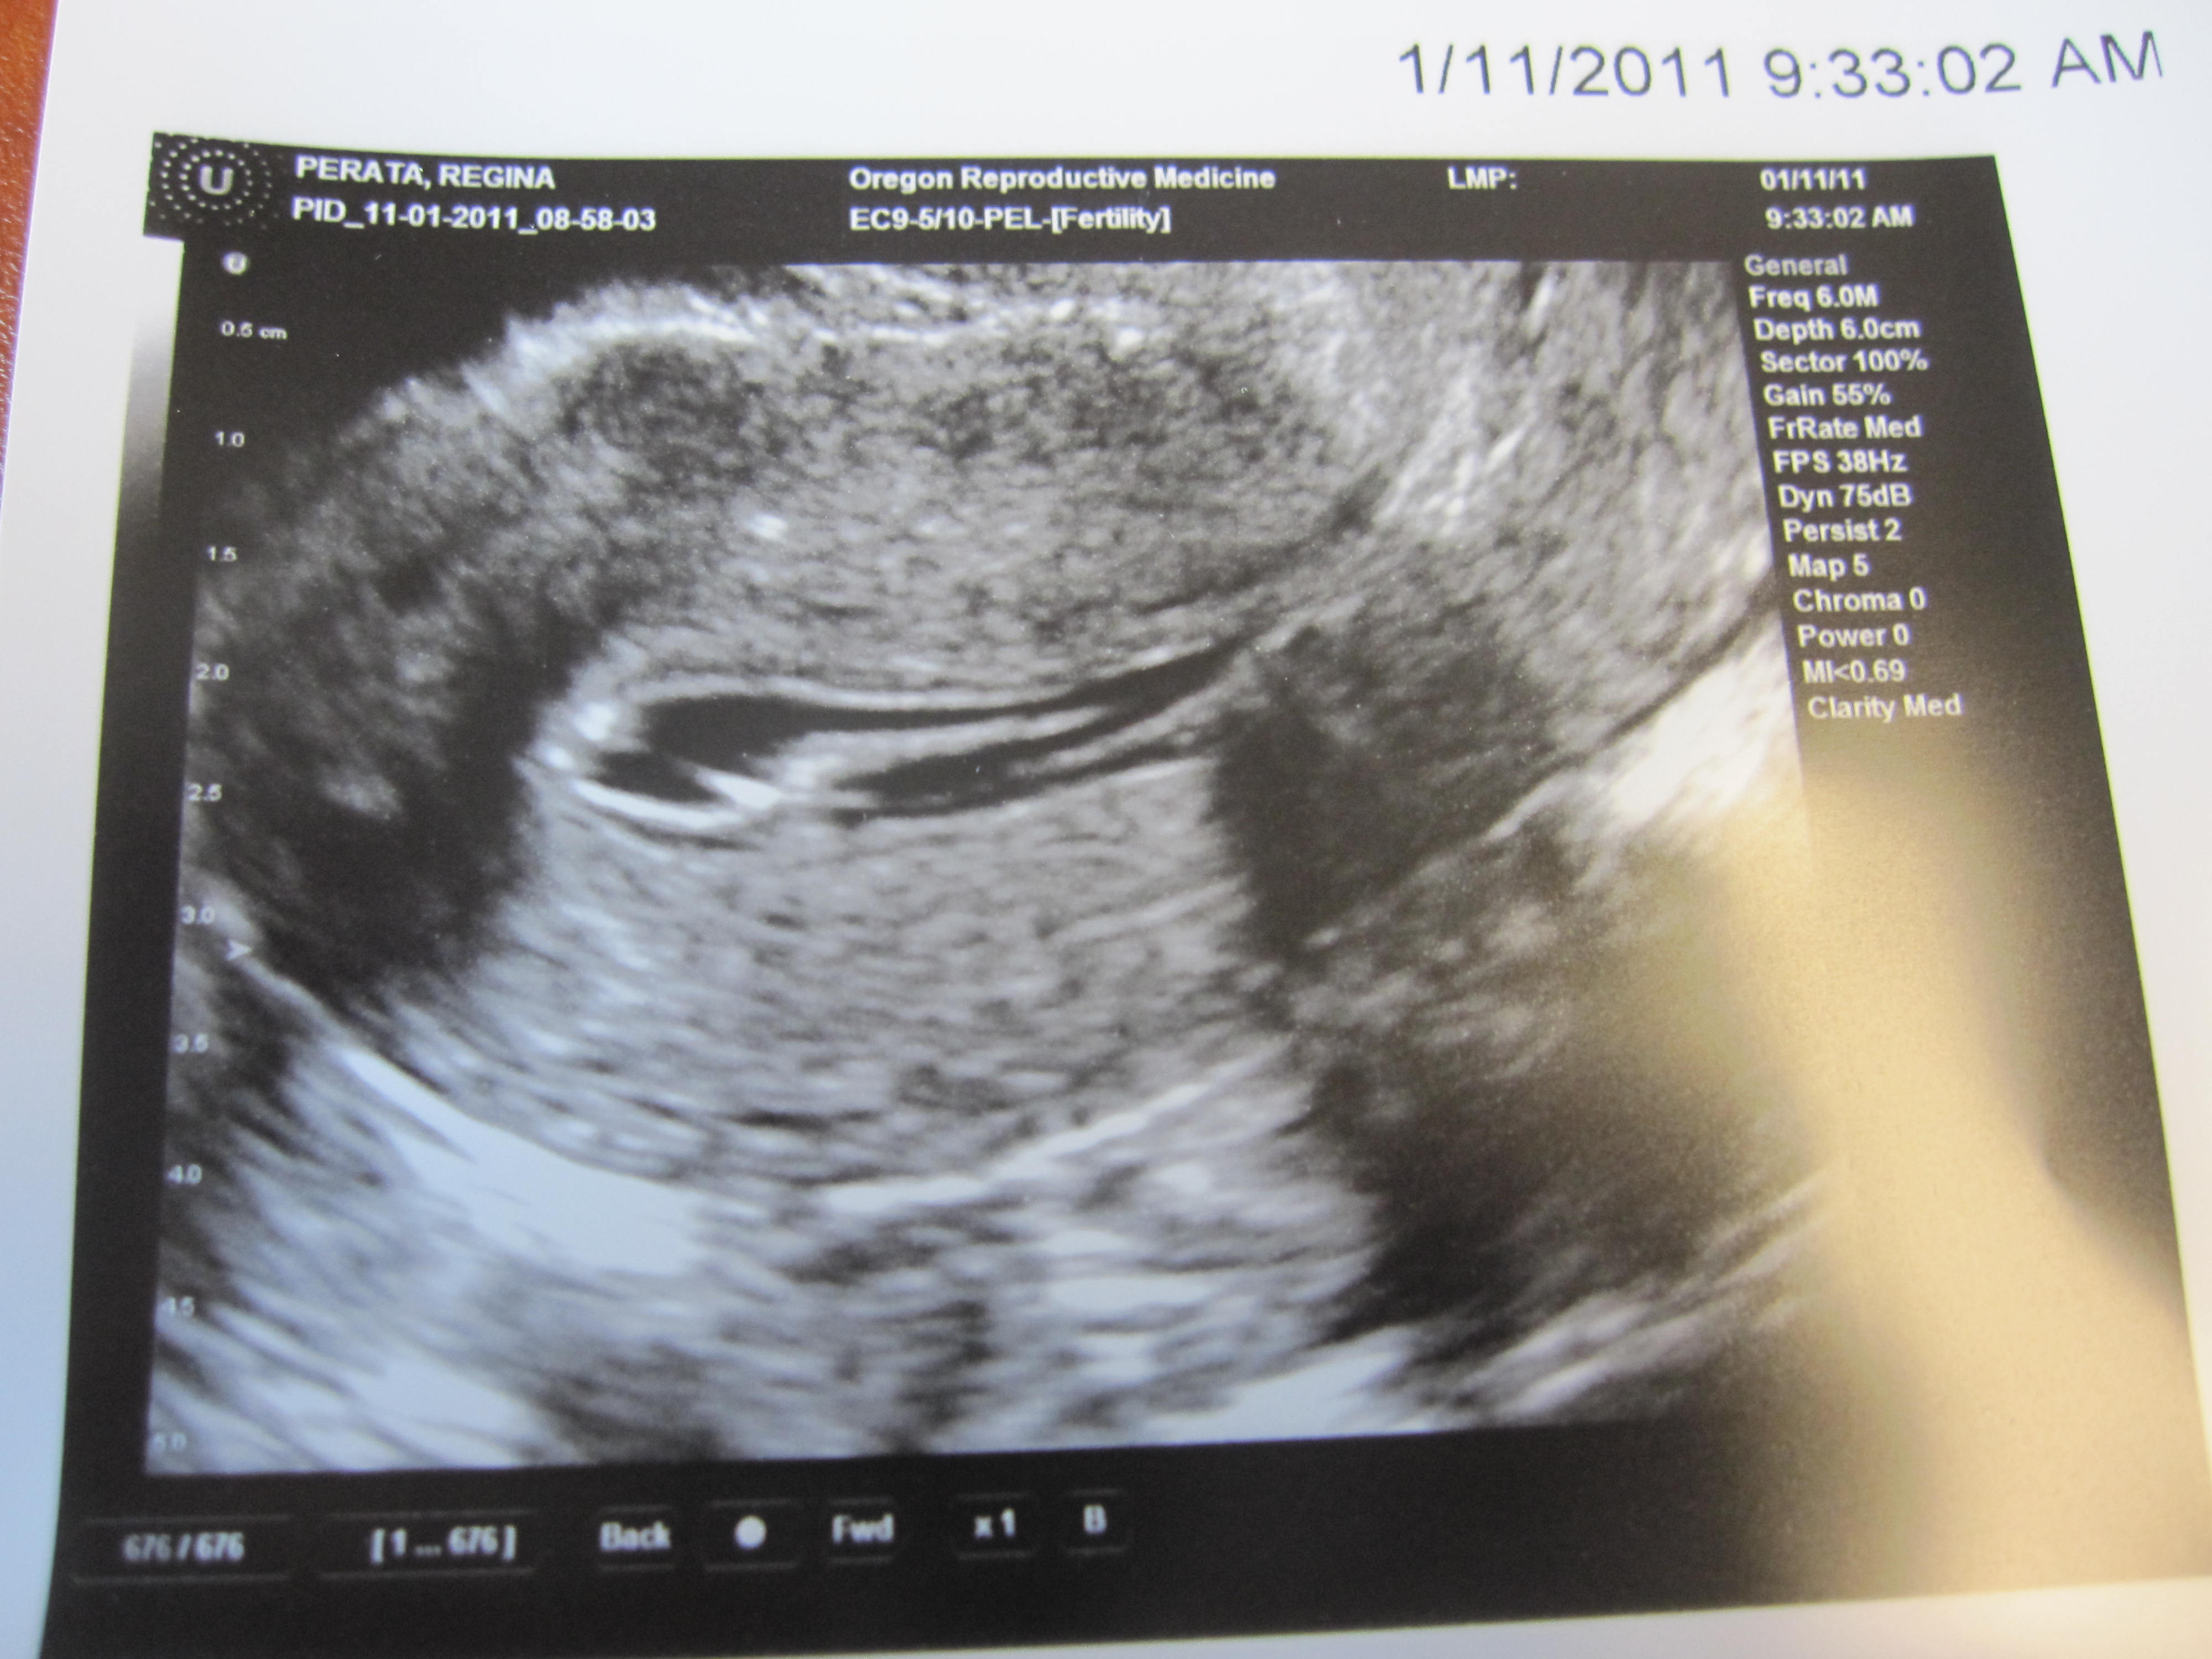

There was a big mass floating around in there. See it down below? The white blob inside the big dark cavity (that is my uterus)?

I always imagined someday I’d get to take these ultrasound pics home, so happy and proud to have a baby growing inside me. Instead, I am now the proud mother of (another) polyp or an enormous blood clot (I’m thinking it’s a clot because my last period was only a tease and I’m pretty sure all my lining didn’t shed- even thought to myself, I should take that herb to help the rest come out).